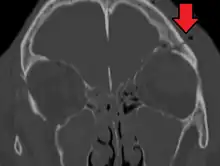

Basilar skull fracture

| A subtle temporal bone fracture as seen on CT in a person with a severe head injury | |

A basilar skull fracture is a break of a bone in the base of the skull.[1] Symptoms may include bruising behind the ears, bruising around the eyes, or blood behind the ear drum.[1] A cerebrospinal fluid (CSF) leak occurs in about 20% of cases and can result in fluid leaking from the nose or ear.[1] Meningitis is a complication in about 14% of cases.[2] Other complications include cranial nerve or blood vessel injury.[1]

They typically require a significant degree of trauma to occur.[1] The break is of at least one of the following bones: temporal bone, occipital bone, sphenoid bone, frontal bone, or ethmoid bone.[1] They are divided into anterior fossa, middle fossa, and posterior fossa fractures.[1] Facial fractures often also occur.[1] Diagnosis is typically by CT scan.[1]

Basilar skull fractures include breaks in the posterior skull base or anterior skull base. The former involve the occipital bone, temporal bone, and portions of the sphenoid bone; the latter, superior portions of the sphenoid and ethmoid bones. The temporal bone fracture is encountered in 75% of all basilar skull fractures and may be longitudinal, transverse or mixed, depending on the course of the fracture line in relation to the longitudinal axis of the pyramid.[6]

The evaluation for basilar skull fracture depends on a CT, as an x-ray is not useful.CT angiography and venography (CTA, CTV) may also be useful as an MRI can be used to ascertain nerve damage[4][8]